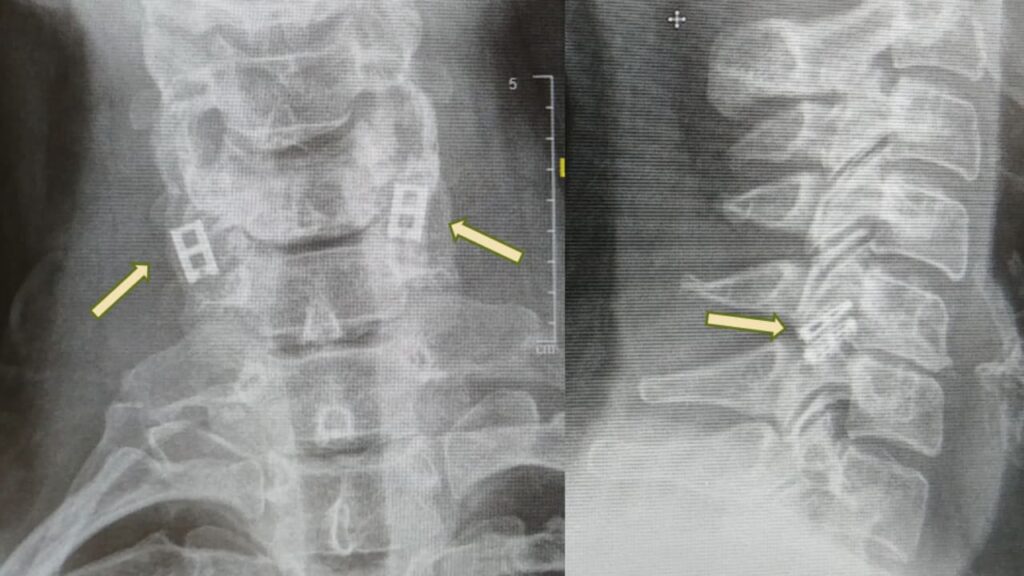

“The spinal cord transmits electrical signals from the brain to all parts of the body. When it is severed by trauma—such as a car accident, a fall, or a combat injury—the chain is broken. Think of an electrical cable that has been cut: when the two ends no longer touch, the signal cannot pass, and the patient remains paralyzed below the injury,” explained Professor Tal Dvir, head of the Sagol Center for Regenerative Biotechnology and the Nanotechnology Center at Tel Aviv University, who is leading the effort. Dvir is also the chief scientist at Matricelf, the Israeli biotech company commercializing the technology.

Unlike other tissues, spinal cord neurons cannot naturally regenerate, and over time, scar tissue blocks remaining signals. The new procedure aims to replace the damaged section with a lab-grown spinal cord that fuses with healthy tissue above and below the injury. Animal studies in rats have shown remarkable results, with the animals regaining the ability to walk normally.